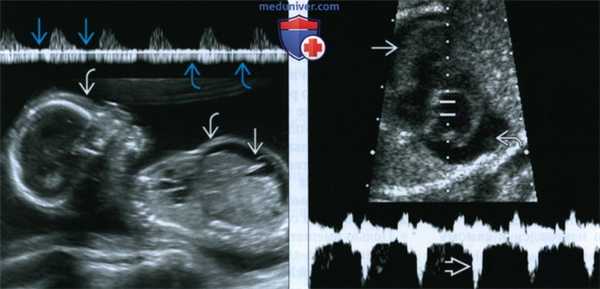

(Слева) СФФТ IV стадии. Длительно существующее шунтирование крови от плода-донора к плоду-реципиенту приводит к перегрузке объемом, в результате которой развивается водянка плода. Определяются утолщение кожи и асцит. Кроме того, обнаружены нарушения при допплеровском исследовании сосудов пуповины: нулевой конечный диастолический кровоток и пульсирующий кровоток в ПВ.

(Справа) Другой случай. Импульсная допплерография. У плода-реципиента определяются признаки сердечной декомпенсации: регургитация ТК, утолщение миокарда и перикардиальный выпот.

(Слева) В основе стадирования СФФТ лежат нарушения гемодинамики, выявляемые с помощью допплерометрии. СФФТ, стадия III-Д. У плода-донора (А) отмечаются нулевой и ретроградный конечный диастолический кровоток, а также пульсирующий кровоток в ПВ. Гемодинамика в пуповине у плода-реципиента (В) не нарушена.

(Справа) Макрофотография плаценты от беременности, осложненной СФФТ. Определяются крупные артериовенозные анастомозы (артерии плода-донора, вены плода-реципиента. Данные глубокие анастомозы на поверхности плаценты граничат «лицом к лицу».